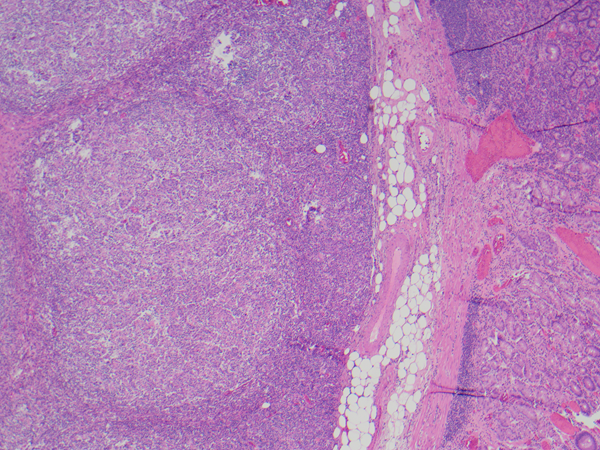

A 74-year-old male with 2 cm gastric mass.

Gastric (adeno)carcinoma with lymphoid stroma is a subtype of gastric carcinoma which has been reported to account for 1 to 7% of gastric carcinomas. This subtype is also referred to as lymphoepithelioma-like carcinoma and medullary carcinoma, and is characterized by irregular sheets, trabeculae or syncytia of polygonal cells embedded within a prominent lymphocytic infiltrate. This tumor is strongly associated with EBV infection and microsatellite instability which are mutually exclusive. PD-L1 is usually overexpressed.